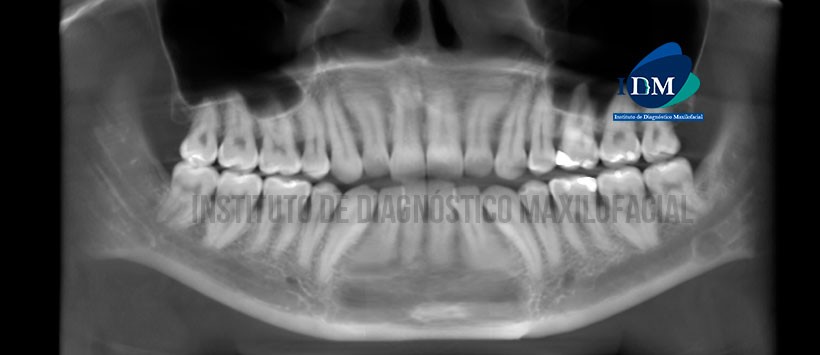

En la reconstrucción panorámica (Figura 1)se observa múltiples restauraciones, ausencia de las terceras molares y una zona hipodensa de forma ovalada y de limites definidos, la cual en su extremo inferior esta en relación con el reborde basal mandibular a nivel de la escotadura antegonial izquierda y en la parte superior en “aparente” contacto con el conducto dentario inferior.